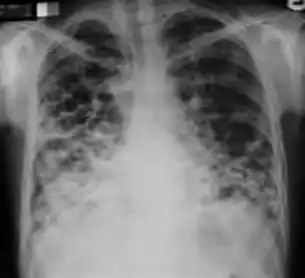

Chest x-ray showing coarse reticulonodular densities on the lower right lung of post-primary pulmonary TB. -